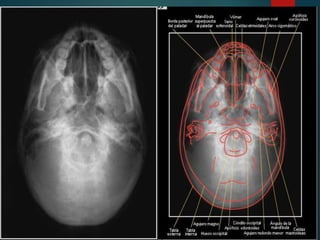

Este documento proporciona instrucciones para realizar diferentes proyecciones radiográficas del cráneo, incluyendo las proyecciones anteroposterior (AP), submentovertex (SMV), parietoorbitaria y transorbitaria de Guillen. Describe los ángulos y posiciones requeridos para cada proyección y las estructuras óseas que deberían ser visibles en cada imagen resultante.